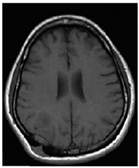

| Sequence | Sequence Characteristics | Main Clinical Distinctions | Example * |

|---|---|---|---|

| T1w | Uses short TR and TE [64] |  | |

| T2w | Uses long TR and TE [64] |  | |

| ceT1w | Uses the same TR and TE as T1w; employs contrast agents [64] |

|  |

| FLAIR | Uses very long TR and TE; the inversion time nulls the signal from fluid [67] |  |